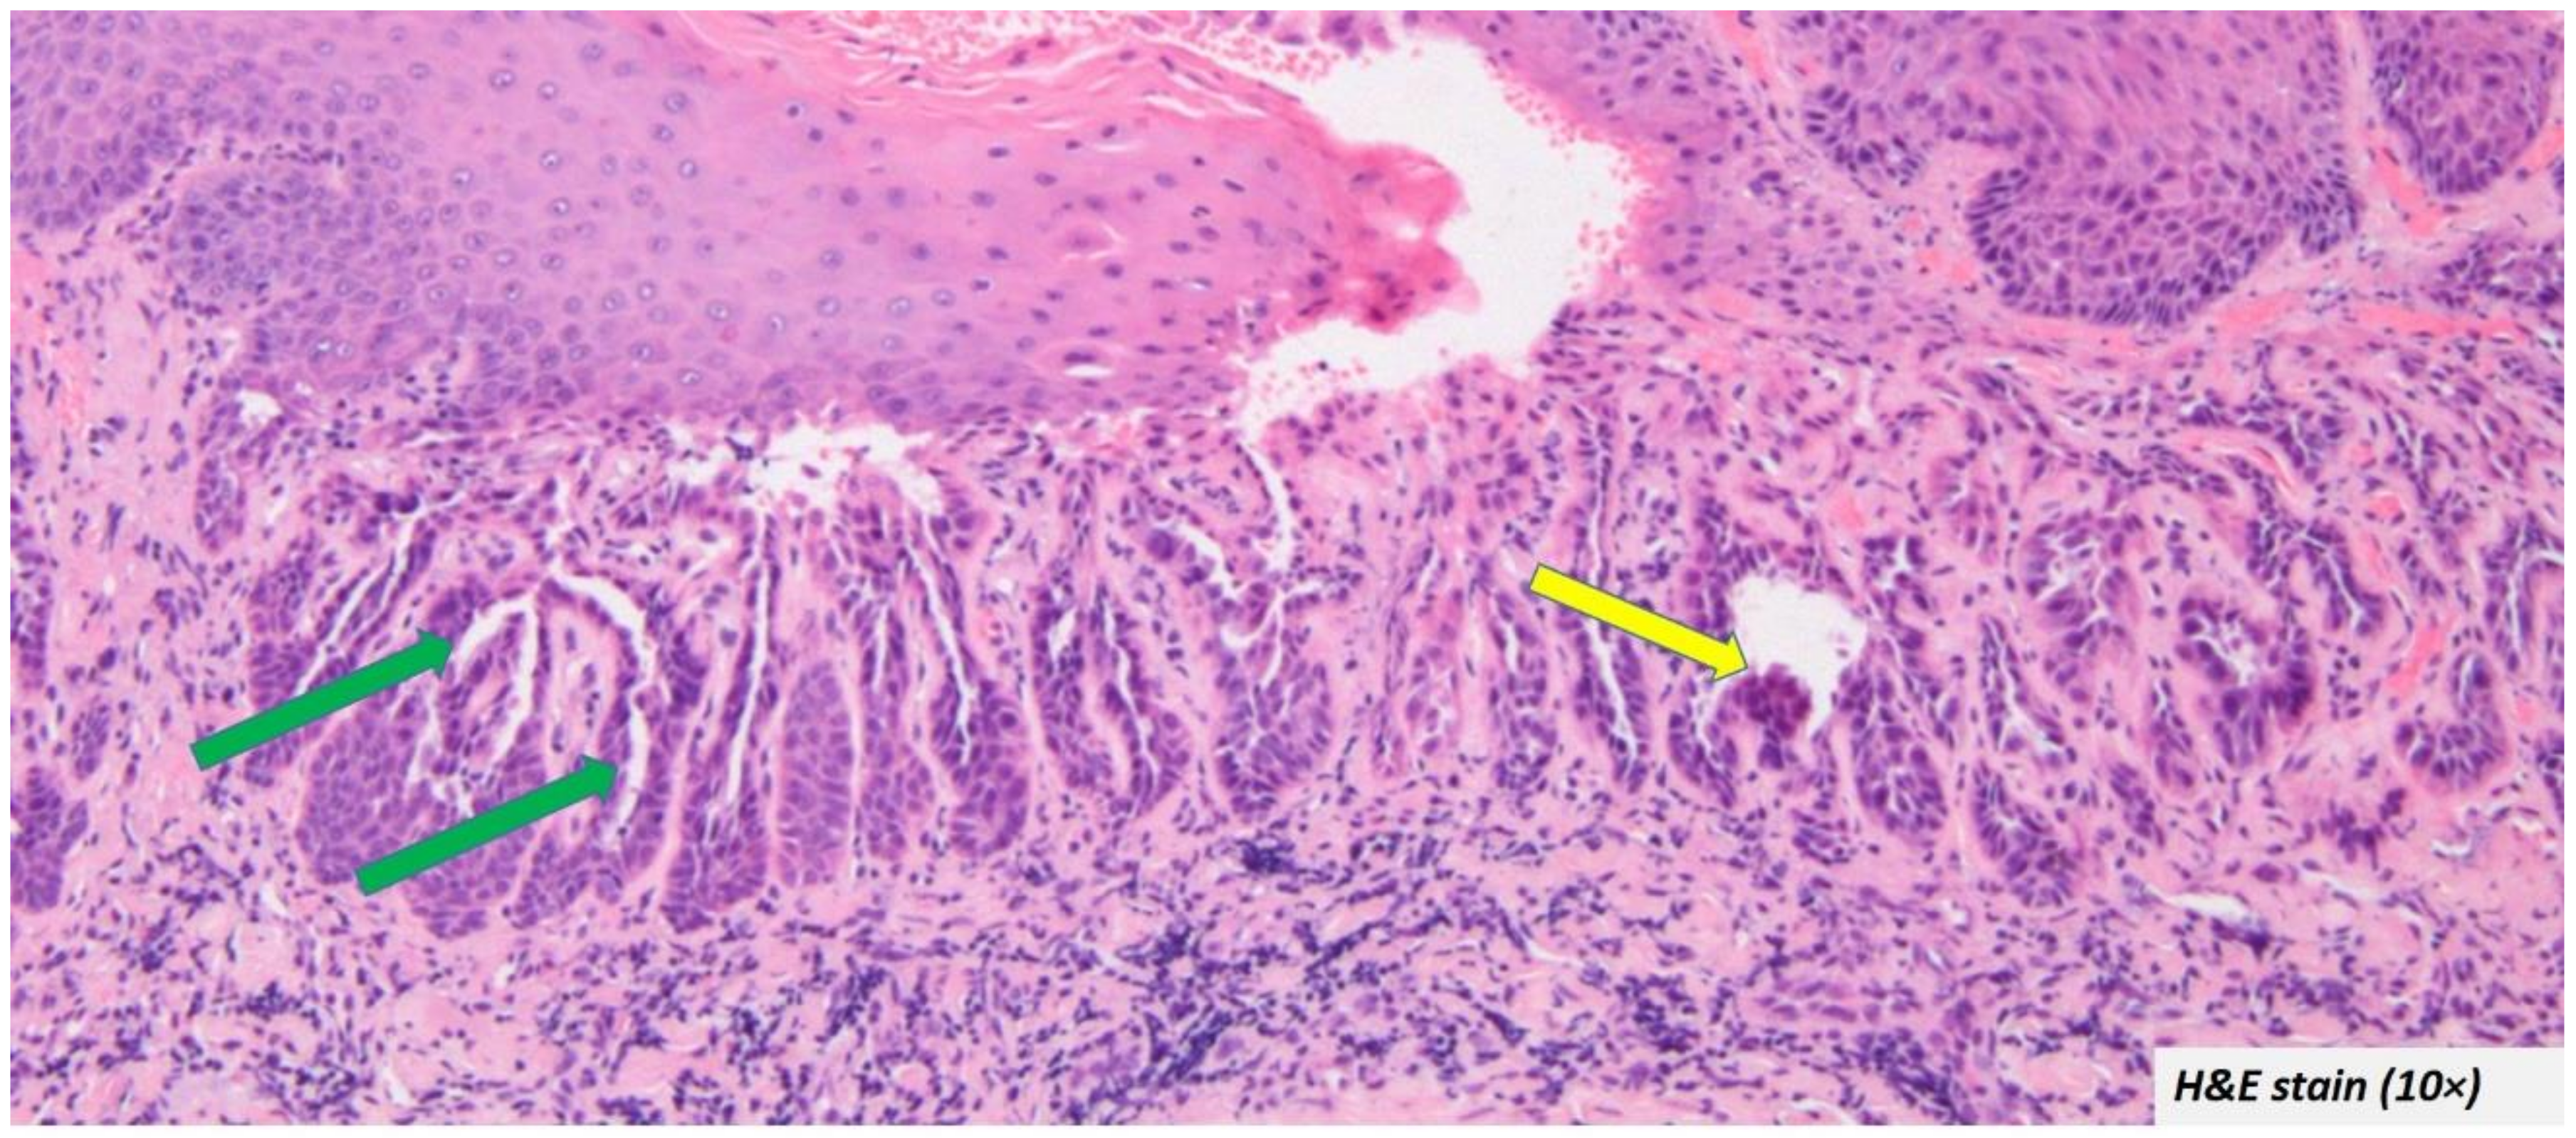

- Common clinical feature includes central depression/crater/umbilicated centre

- Common histopathological features include supra-basal clefting, keratin-filled crypts, corps ronds, and grains